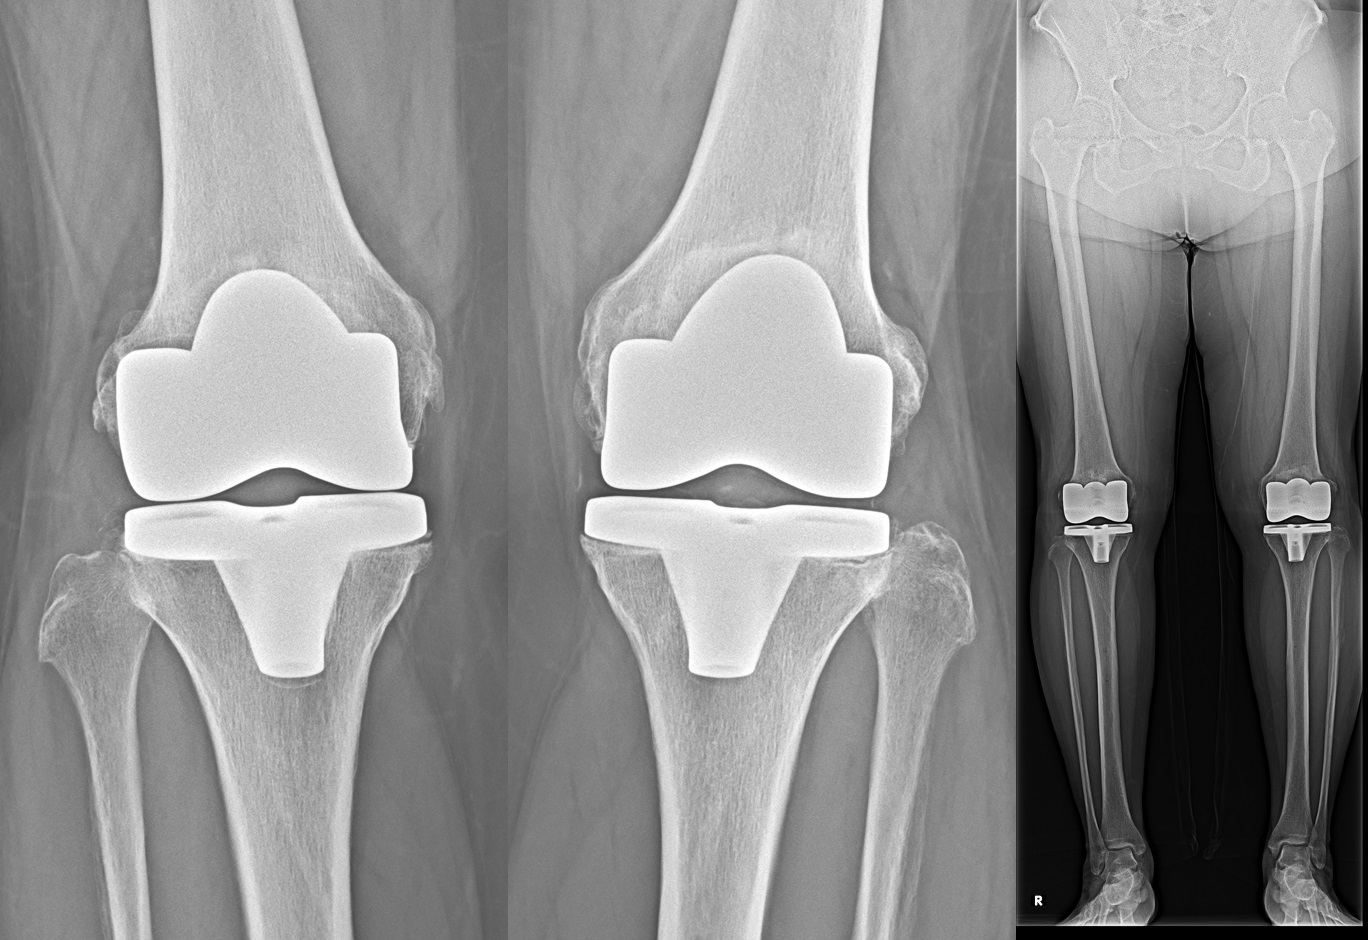

人工膝関節全置換術(total knee arthroplasty: TKA)

末期の変形性膝関節症に対してはTKAを行います。

術前の膝の状態を考慮した上で、それぞれに適切な機種および術式を選択しております。

人工膝関節全置換術における3Dテンプレート・動作解析

当院では3次元術前計画ソフトウェア(LEXI社 Zedknee)を用いて患者様のCT画像から最適なインプラントの種類やサイズを手術前から把握することが出来るためより正確な手術が可能となりました。また、膝関節の動態解析が可能ですので術後の状態をより詳細に把握し、リハビリに還元することが可能です。